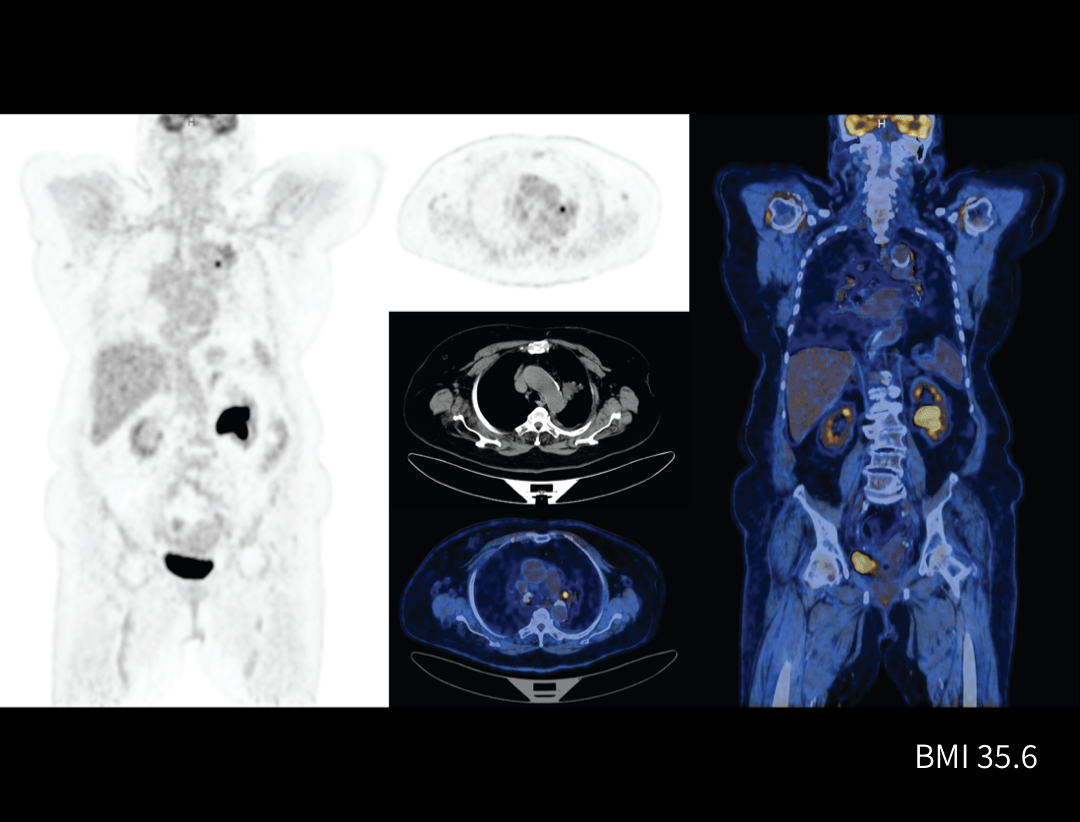

Galerie clinică

Limfom

Tehnologia PET/CT digitală joacă un rol crucial în diagnosticarea și monitorizarea limfomului, oferind imagini de înaltă rezoluție pentru detectarea leziunilor și evaluarea eficienței tratamentului.